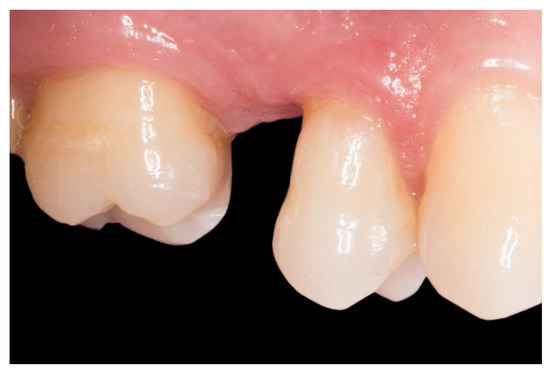

Figure 2.

The proximal faces of the adjacent teeth delimiting the edentulous space carved up to the level of the ideal point of contact (inlay cavities).

2. The proximal faces of the adjacent teeth delimiting the edentulous space were carved up to the level of the ideal point of contact (inlay cavities), to position the future horizontal structure of the fiberglass bridge (Figure 2).